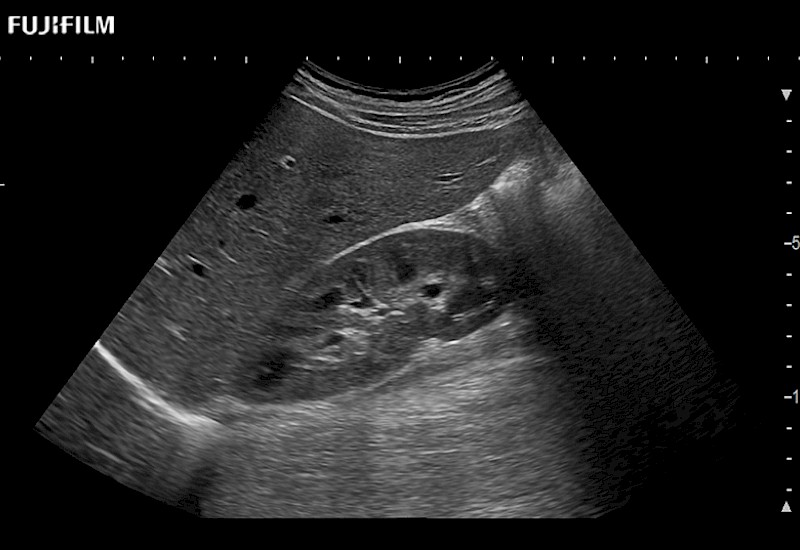

for use during open and laparoscopic procedures: Tumor localization & staging, Ablation, Resection, Biopsy, Transplant, Abdominal exploration, Robotic surgery

Our dedication to Surgical Oncology allows us to offer superior image quality, outstanding system reliability and intuitive use of cutting edge technology.